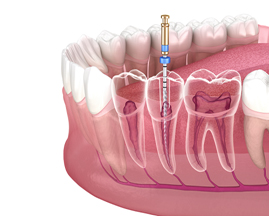

根管治療とは

根管治療とは、深い虫歯や歯の亀裂、外傷などの原因により、歯の根の中の歯髄(神経や血管など)が炎症や感染を起こした際に施す治療法です。歯髄が生きている場合は、冷たい水や熱いものが強くしみたり、ズキズキと強い痛みがあったり、歯と歯を咬み合わせられない程の痛みが出ます。これは「急性歯髄炎」という状態で、その場合は早急に根管治療を行わないと痛みが取れません。

また、上記のような状態を放置していると、歯髄が壊死・感染を引き起こし、根管を通じて、歯を支えている歯槽骨に炎症・感染が波及する場合があります。これは「根尖性歯周炎」という状態で、歯肉が部分的に少し腫れたり、咬合痛がでることがあります。上記の急性歯髄炎のような強い痛みが出ない場合がありますが、早急に根管治療を行わないと、歯槽骨内の感染が拡大し、悪い場合は抜歯に至るケースもあります。

根管は細く複雑な形状をしており、歯によって根管の数が複数ある場合があります。そのため根管治療は、非常に難しく、高い精度が求められる治療法と言えます。

根管治療の流れについて

① 根管拡大・洗浄

拡大鏡を用いて拡大視野下にて、ファイルと呼ばれる根管の形に即した器具で、根管内の感染組織を物理的に除去します。

また次亜塩素酸ナトリウムにて根管内を化学的に洗浄します。

② 根管形成・根管充填

上記の根管拡大・洗浄を十分に行い、感染組織を除去した後、最終的には根管内にガッタパーチャと呼ばれる密閉性の高い詰め物で根管内を充填します。根管の先まで緊密に充填できるように根管をファイルにて形成します。